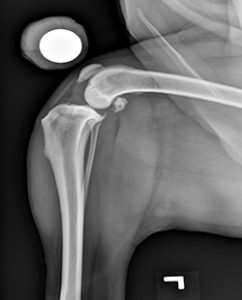

Diagnosing complete tears of the CCL is easily accomplished by a combination of observation of your pet’s gait, palpation of the knee and radiographs (X-rays). For early partial tears, however, it can be a bit more complicated and may sometimes require advanced imaging such as MRI or surgical exploration to physically look at the ligament. X-rays are usually taken to confirm the presence of joint effusion (fluid accumulation in the joint which indicates that there is a problem within the joint), the degree of arthritis, to aid in surgical planning and to rule out concurrent disease conditions such as bone cancer. For certain treatments, like tibial plateau leveling osteotomy (TPLO) and tibial tuberosity advancement (TTA), specific X-rays are required and your surgeon may need to repeat radiographs of the knee even if your veterinarian has already taken some. Specific palpation techniques that veterinarians use to confirm a problem with the CCL are the “cranial drawer test” and the “tibial thrust test.” These tests confirm abnormal motion in the knee and hence a rupture of the CCL. X-rays do not show the status (i.e. intact or damaged) of the CCL or the meniscus because those structures cannot be seen on X-rays. Therefore, it is crucial that the surgeon evaluate both of these structures (meniscus and the cruciate ligament) when performing the chosen surgical repair. This can be done either via an arthrotomy (opening of the joint) or with the use of a minimally-invasive camera (arthroscope) and is generally combined with the surgical procedure itself because both procedures require full anesthesia and clipping of the animal.

Tibial plateau leveling osteotomy (TPLO) involves making a circular cut in the tibial plateau and rotating the contact surface of this bone until it attains a relatively level orientation that puts it at approximately 90 degrees to the attachment of the quadriceps muscles (see Figure 2). This orientation of the tibial plateau renders the knee relatively stable, independent of the CCL. The cut in the bone needs to be stabilized by the use of a bridging bone plate and screws. Once the bone has healed, the bone plate and screws are not needed, but are seldom removed unless there is an associated problem. The greatest advantage of this technique is the perceived superior outcome (limb function and less progression of arthritis) compared to traditional suture techniques especially in young, large breed dogs. The major disadvantage is the need to perform an osteotomy. Any osteotomy requires healing of the bone and if a problem is observed (such as implant failure, failure of the bone to heal), it may require multiple revision surgeries and the outcome may be poor. Luckily, such complications are rare, especially when the procedure is performed by an experienced surgeon.